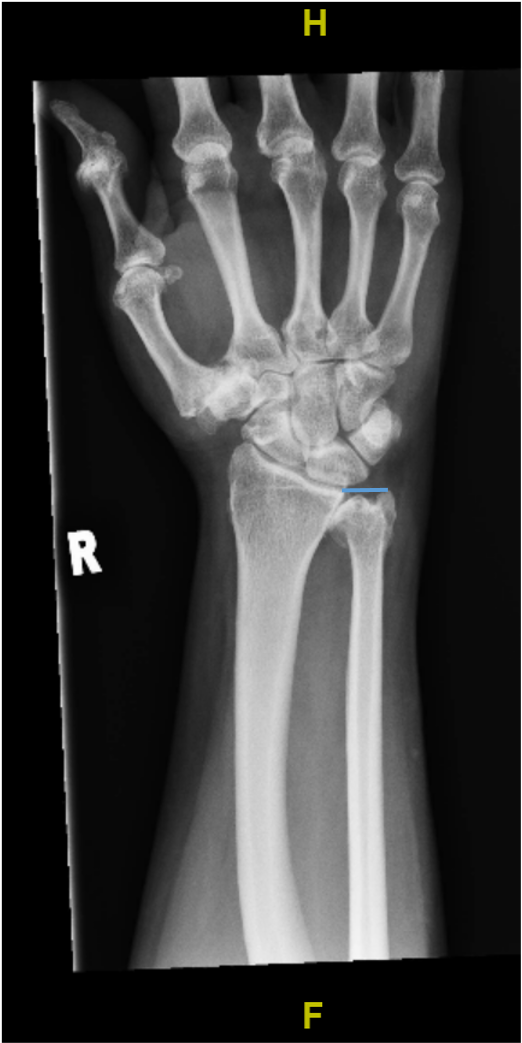

Radiographs of the right hand and wrist demonstrated negative ulnar variance, with severe osteoarthritic changes of the DRUJ evidenced by marginal osteophytes, joint-space narrowing, and subchondral sclerosis on either side of the joint (Figures 1 and 2). Mild deformity of the distal ulnar also raised the possibility of previously unrecalled trauma.

Figure 1. Anteroposterior radiograph of the right wrist, demonstrating negative ulnar variance. The blue horizontal line drawn from the carpal joint surface of the distal radius towards the ulna demonstrates that the distal edge of the ulna is proximal to the distal articular surface of the radius. Mild deformity of the distal ulna may be related to previous unrecalled trauma.